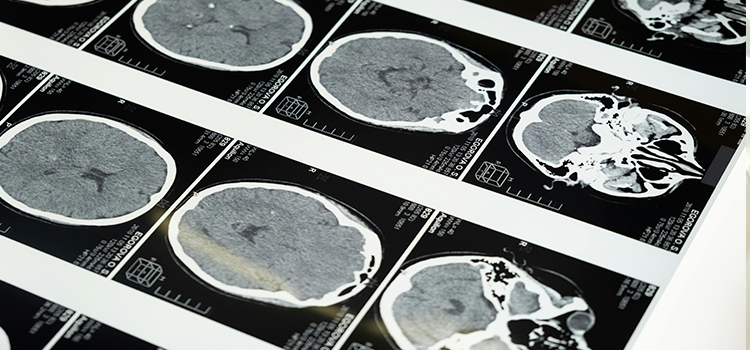

Expresión de uno de los factores de Yamanaka, Klf4, en un corte transversal del cerebro de uno de los ratones transgénicos con expresión condicional del transgén que contiene los factores.